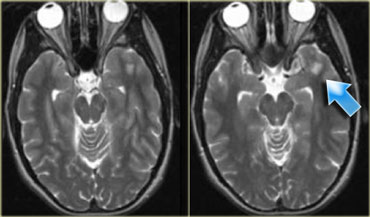

On the left some examples of tumors with a low signal intensity on T2WI.

1. Melanoma metastases have a low SI on T2WI as a result of the melanin.

2. GBM can have a low SI on T2WI because sometimes they have a high nuclear-cytoplasmic ratio. Most GBM's, however, are hyperintense on T2WI.

3. PNET typically has a high nuclear-cytoplasmic ratio. PNET is mostly located in the region of the 4th ventricle, but another, less common, location is in the region of the pineal gland.

4. Mucinous metastases can have a low SI on T2WI because they often contain calcifications..

5. Meningiomas are mostly of intermediate signal.

They can have a high SI on T2WI if they contain a lot of water.

They can have a low SI on T2WI if they are very dense and hypercellular or when they contain calcifications.